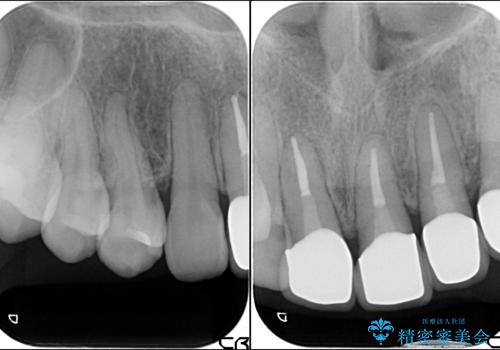

- 前歯の歯肉の高さが左右で異なっていることを気にして来院された患者様です。

歯肉レベルを調整するために歯周外科処置をおこない、その後にオールセラミッククラウンにて補綴することとしました。

歯肉の位置を整えるには歯周外科処置が必要であると説明した際には、なかなか踏み切ることができず、大変悩まれていました。

処置後の痛みはあまり気にならず、歯肉位置の左右差もほとんどなくなり、患者様には大変満足していただきました。